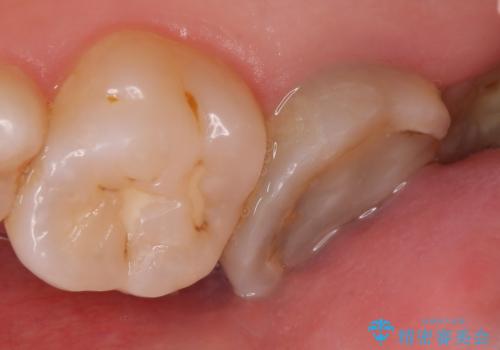

オールセラミッククラウン 鈍痛が続く奥歯の治療

- 他院にて右上7番目の歯の根管治療を行ったが鈍い痛みが治まらないので診て欲しいといらっしゃった方の症例です。

再根管治療を行い症状の消失を確認後、オールセラミッククラウンによる補綴を行いました。

今回用いたオールセラミッククラウンはジルコニアフレームという白い素材の上にセラミックを盛っているため、審美性が非常に高いのが特徴です。

また、ジルコニアは人工ダイヤモンドの材料にも使われているほど高い強度を持っており、そのためオールセラミッククラウンは審美性だけでなく、奥歯やブリッジの補綴も可能とするクラウンです。